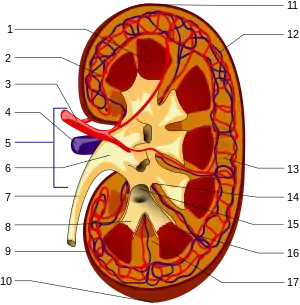

In clearance, or the rate at which a substance is removed or cleared from the body, it has been found that the cellular proteolysis of AGEs—the breakdown of proteins—produces AGE peptides and "AGE free adducts" (AGE adducts bound to single amino acids). These latter, after being released into the plasma, can be excreted in the urine.[34]

Nevertheless, the resistance of extracellular matrix proteins to proteolysis renders their advanced glycation end products less conducive to being eliminated.[34] While the AGE free adducts are released directly into the urine, AGE peptides are endocytosed by the epithelial cells of the proximal tubule and then degraded by the endolysosomal system to produce AGE amino acids. It is thought that these acids are then returned to the kidney's inside space, or lumen, for excretion. [22] AGE free adducts are the major form through which AGEs are excreted in urine, with AGE-peptides occurring to a lesser extent[22] but accumulating in the plasma of patients with chronic kidney failure.[34]

Larger, extracellularly derived AGE proteins cannot pass through the basement membrane of the renal corpuscle and must first be degraded into AGE peptides and AGE free adducts. Peripheral macrophage[22] as well as liver sinusoidal endothelial cells and Kupffer cells [35] have been implicated in this process, although the real-life involvement of the liver has been disputed. [36]

Large AGE proteins unable to enter the Bowman's capsule are capable of binding to receptors on endothelial and mesangial cells and to the mesangial matrix.[22] Activation of RAGE induces production of a variety of cytokines, including TNFβ, which mediates an inhibition of metalloproteinase and increases production of mesangial matrix, leading to glomerulosclerosis[23] and decreasing kidney function in patients with unusually high AGE levels.

Although the only form suitable for urinary excretion, the breakdown products of AGE—that is, peptides and free adducts—are more aggressive than the AGE proteins from which they are derived, and they can perpetuate related pathology in diabetic patients, even after hyperglycemia has been brought under control.[22]

Some AGEs have an innate catalytic oxidative capacity, while activation of NAD(P)H oxidase through activation of RAGE and damage to mitochondrial proteins leading to mitochondrial dysfunction can also induce oxidative stress. A 2007 in vitro study found that AGEs could significantly increase expression of TGF-β1, CTGF, Fn mRNA in NRK-49F cells through enhancement of oxidative stress, and suggested that inhibition of oxidative stress might underlie the effect of ginkgo biloba extract in diabetic nephropathy. The authors suggested that antioxidant therapy might help prevent the accumulation of AGEs and induced damage.[23] In the end, effective clearance is necessary, and those suffering AGE increases because of kidney dysfunction might require a kidney transplant.[22]

In diabetics who have an increased production of an AGE, kidney damage reduces the subsequent urinary removal of AGEs, forming a positive feedback loop that increases the rate of damage. In a 1997 study, diabetic and healthy subjects were given a single meal of egg white (56 g protein), cooked with or without 100 g of fructose; there was a greater than 200-fold increase in AGE immunoreactivity from the meal with fructose.[37]